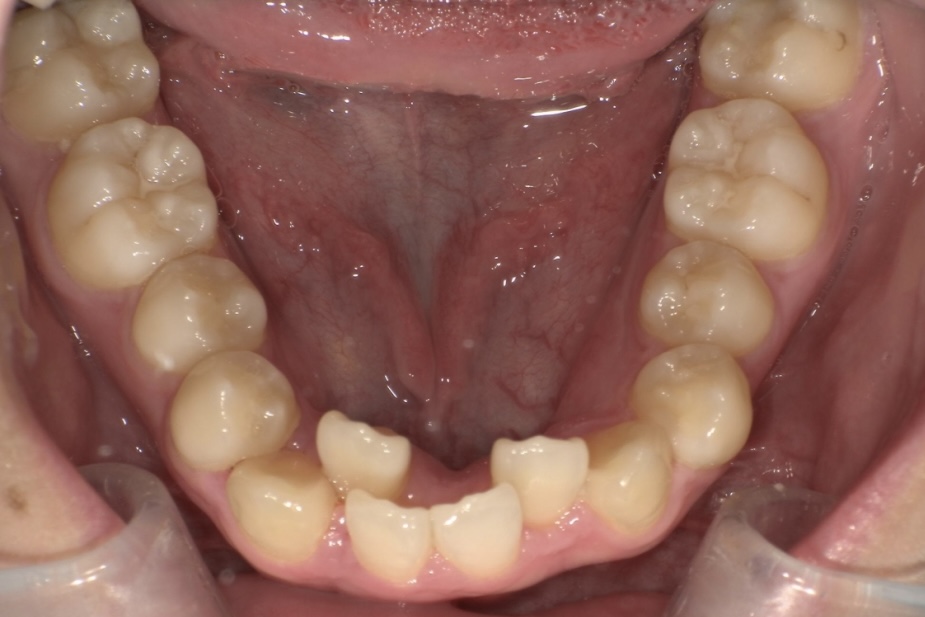

BEFORE

大学生の女性の患者さまで、ガタガタした歯並びをできるだけ痛みの少ない方法で整えたいとご相談に来院されました。

| 主訴 | ガタガタの歯並びが気になる |